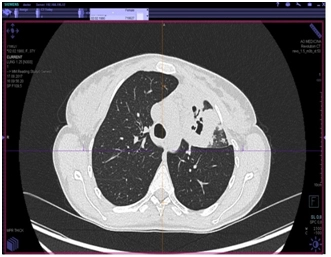

КТ органов грудной клетки (от 17.08.2017 г.)

Заключение: массивные инфильтративные изменения в верхней доле левого легкого полностью неясного генеза, возможно имеет место как воспалительный специфический характер поражения с распадом, так и осложнение пневмонии с формированием абсцесса, злокачественный процесс с распадом мало вероятен.